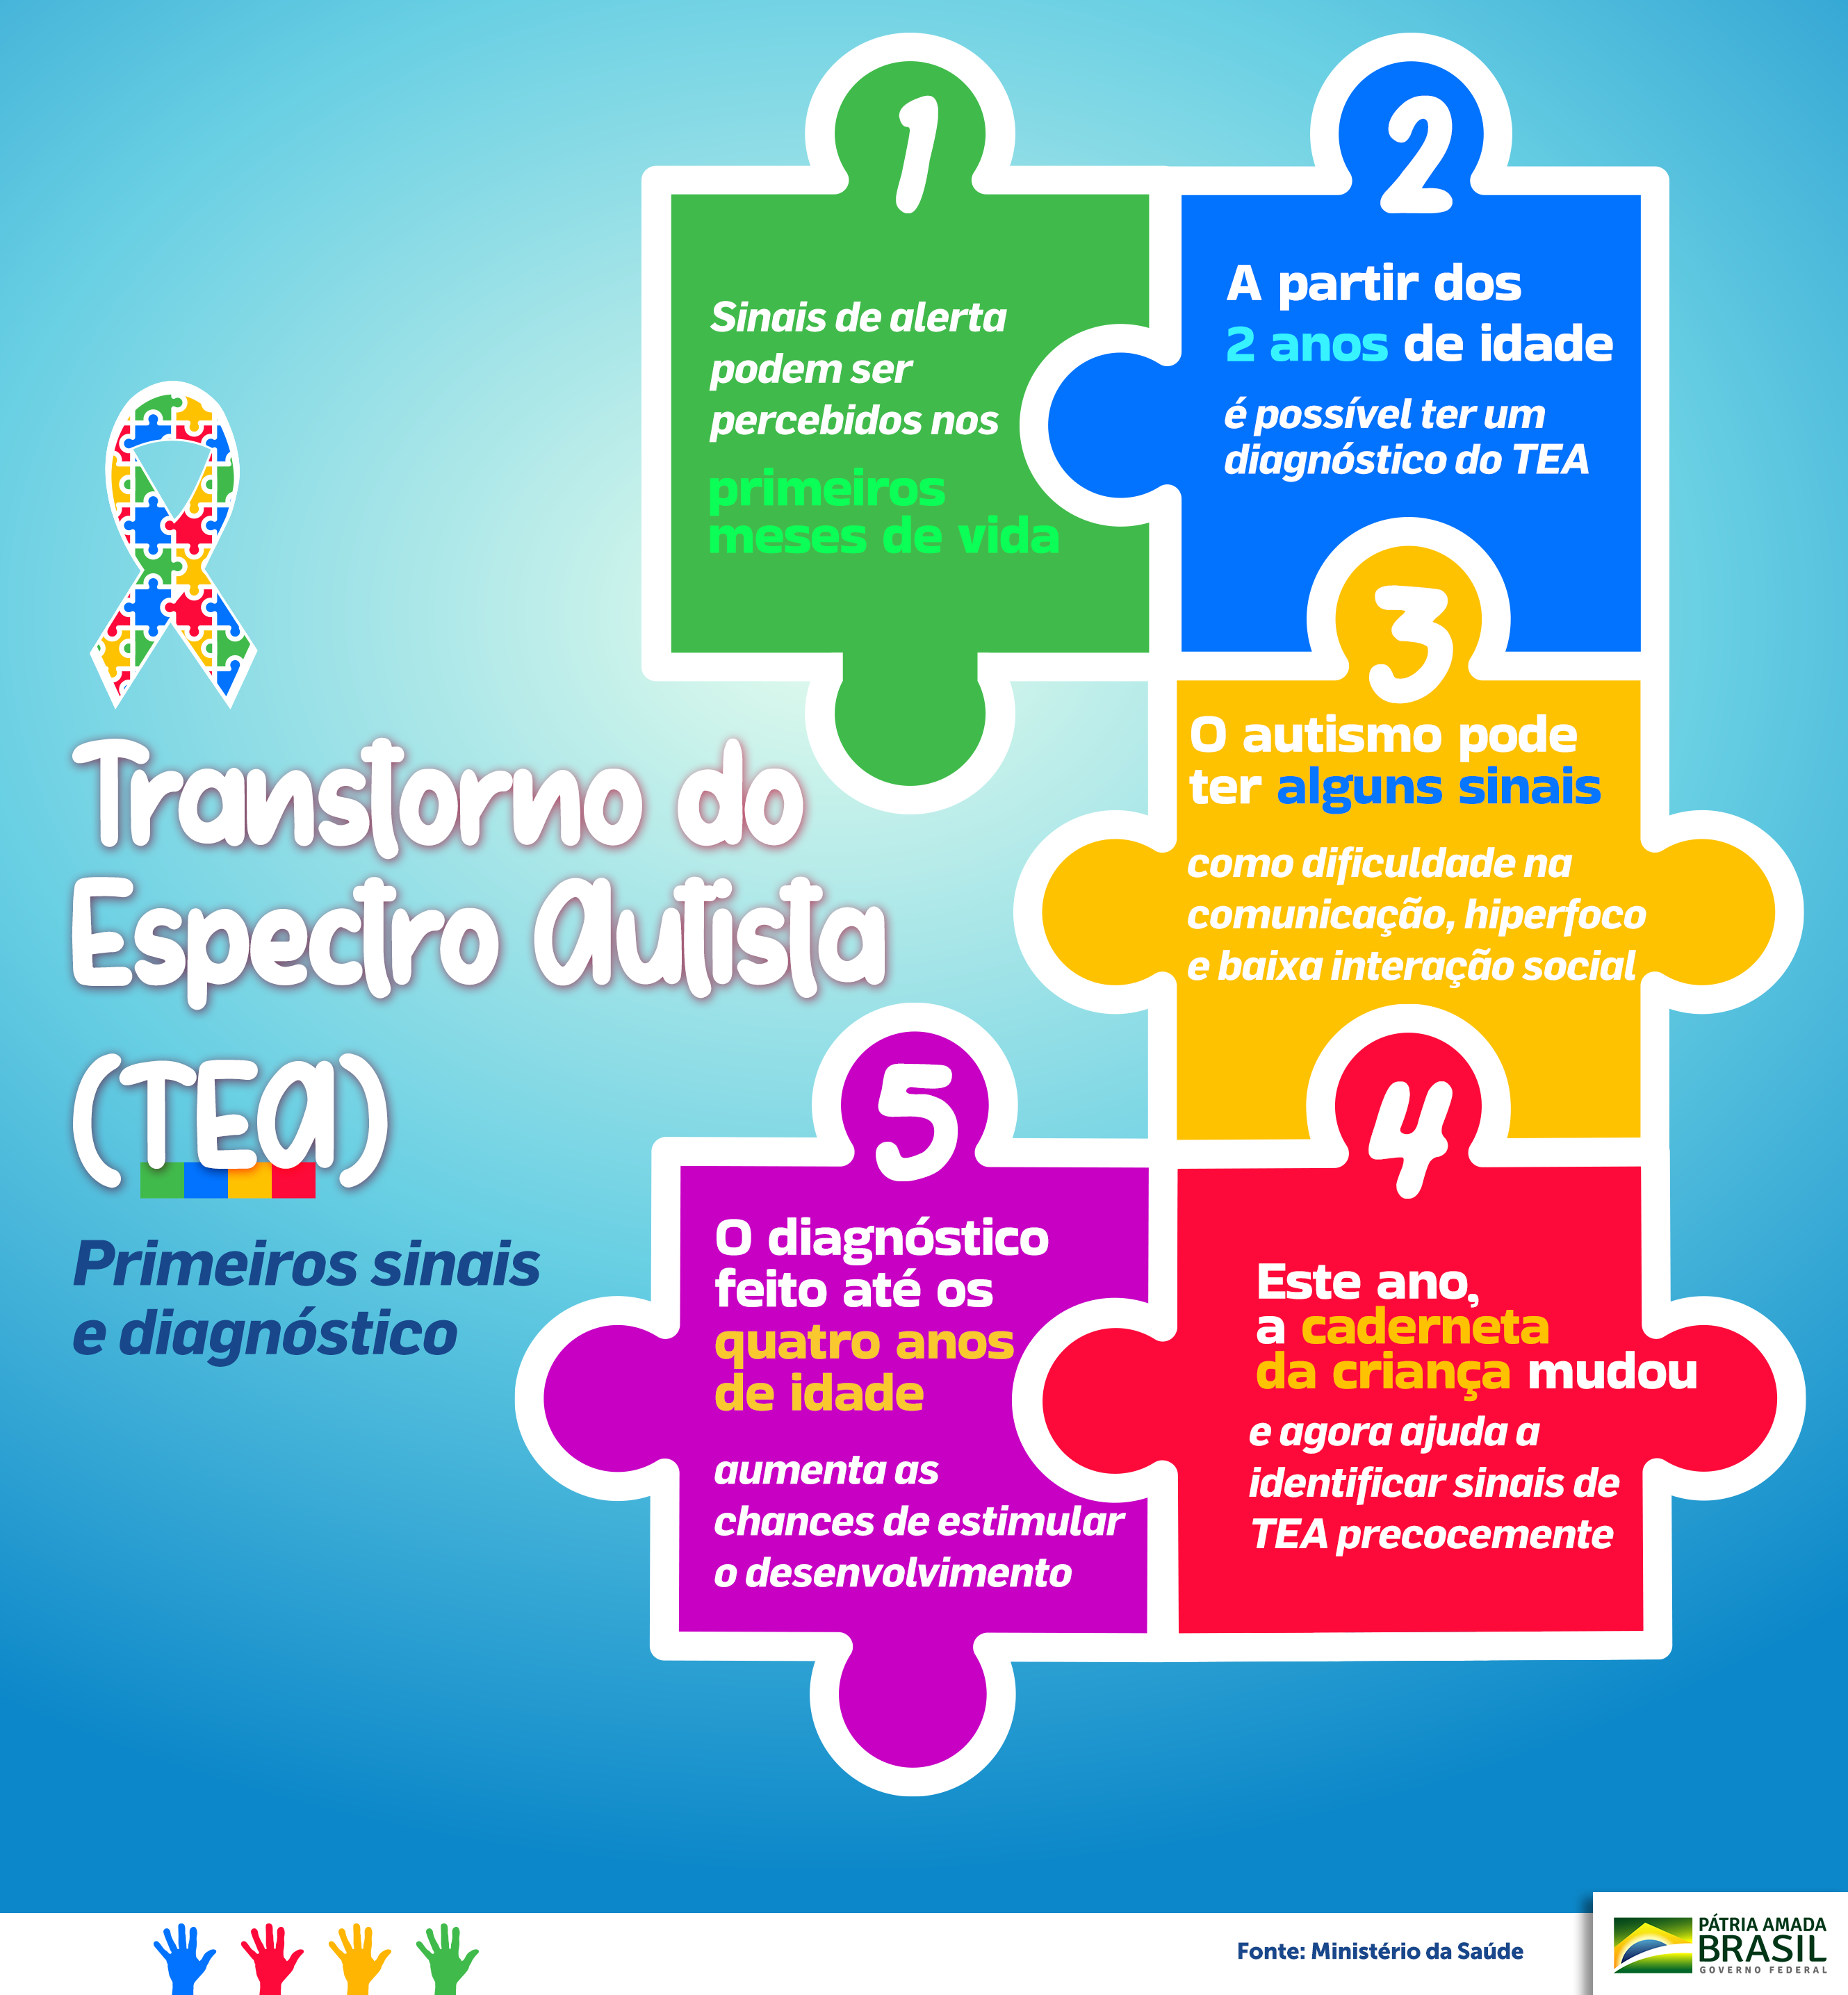

Ainda que haja somente suspeita clínica, quanto mais precoce se inicia o tratamento, maior a qualidade de vida Em geral, a partir de um ano e meio de idade, alguns sinais de autismo — ou Transtorno do Espectro do Autismo, seu nome técnico — já podem aparecer, até mesmo mais cedo em casos mais graves. Há uma grande importância de se iniciar o tratamento o quanto antes, objetivando intervenção terapêutica adequada, mesmo que haja somente uma suspeita clínica, pois quanto antes iniciem-se as intervenções, maior será a qualidade de vida da pessoa. (saiba mais no nosso artigo “O que é

O Transtorno do Espectro do Autismo (TEA)

Conheça os Sinais do Autismo

Conheça os primeiros sinais do Autismo! - Blog Rhema Educação04 abril 2025

Vigilância em saúde - TEA04 abril 2025